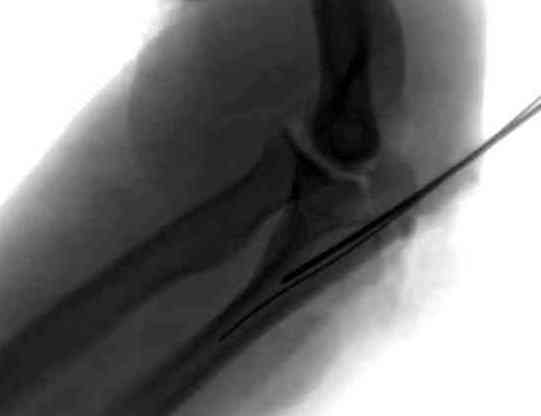

Здесь выставлены несколько случаев и варианты фиксации локтевого отростка, некоторые в комбинации с другими переломами.

1 вариант применен ACUMED локинг пластина

2 вариант

перелом локтевого отростка с переломом головки лучевой кости (использованы 2 мм шурупы)

3 вариант

перелом с capitelum humerus и проксимальной трети улна